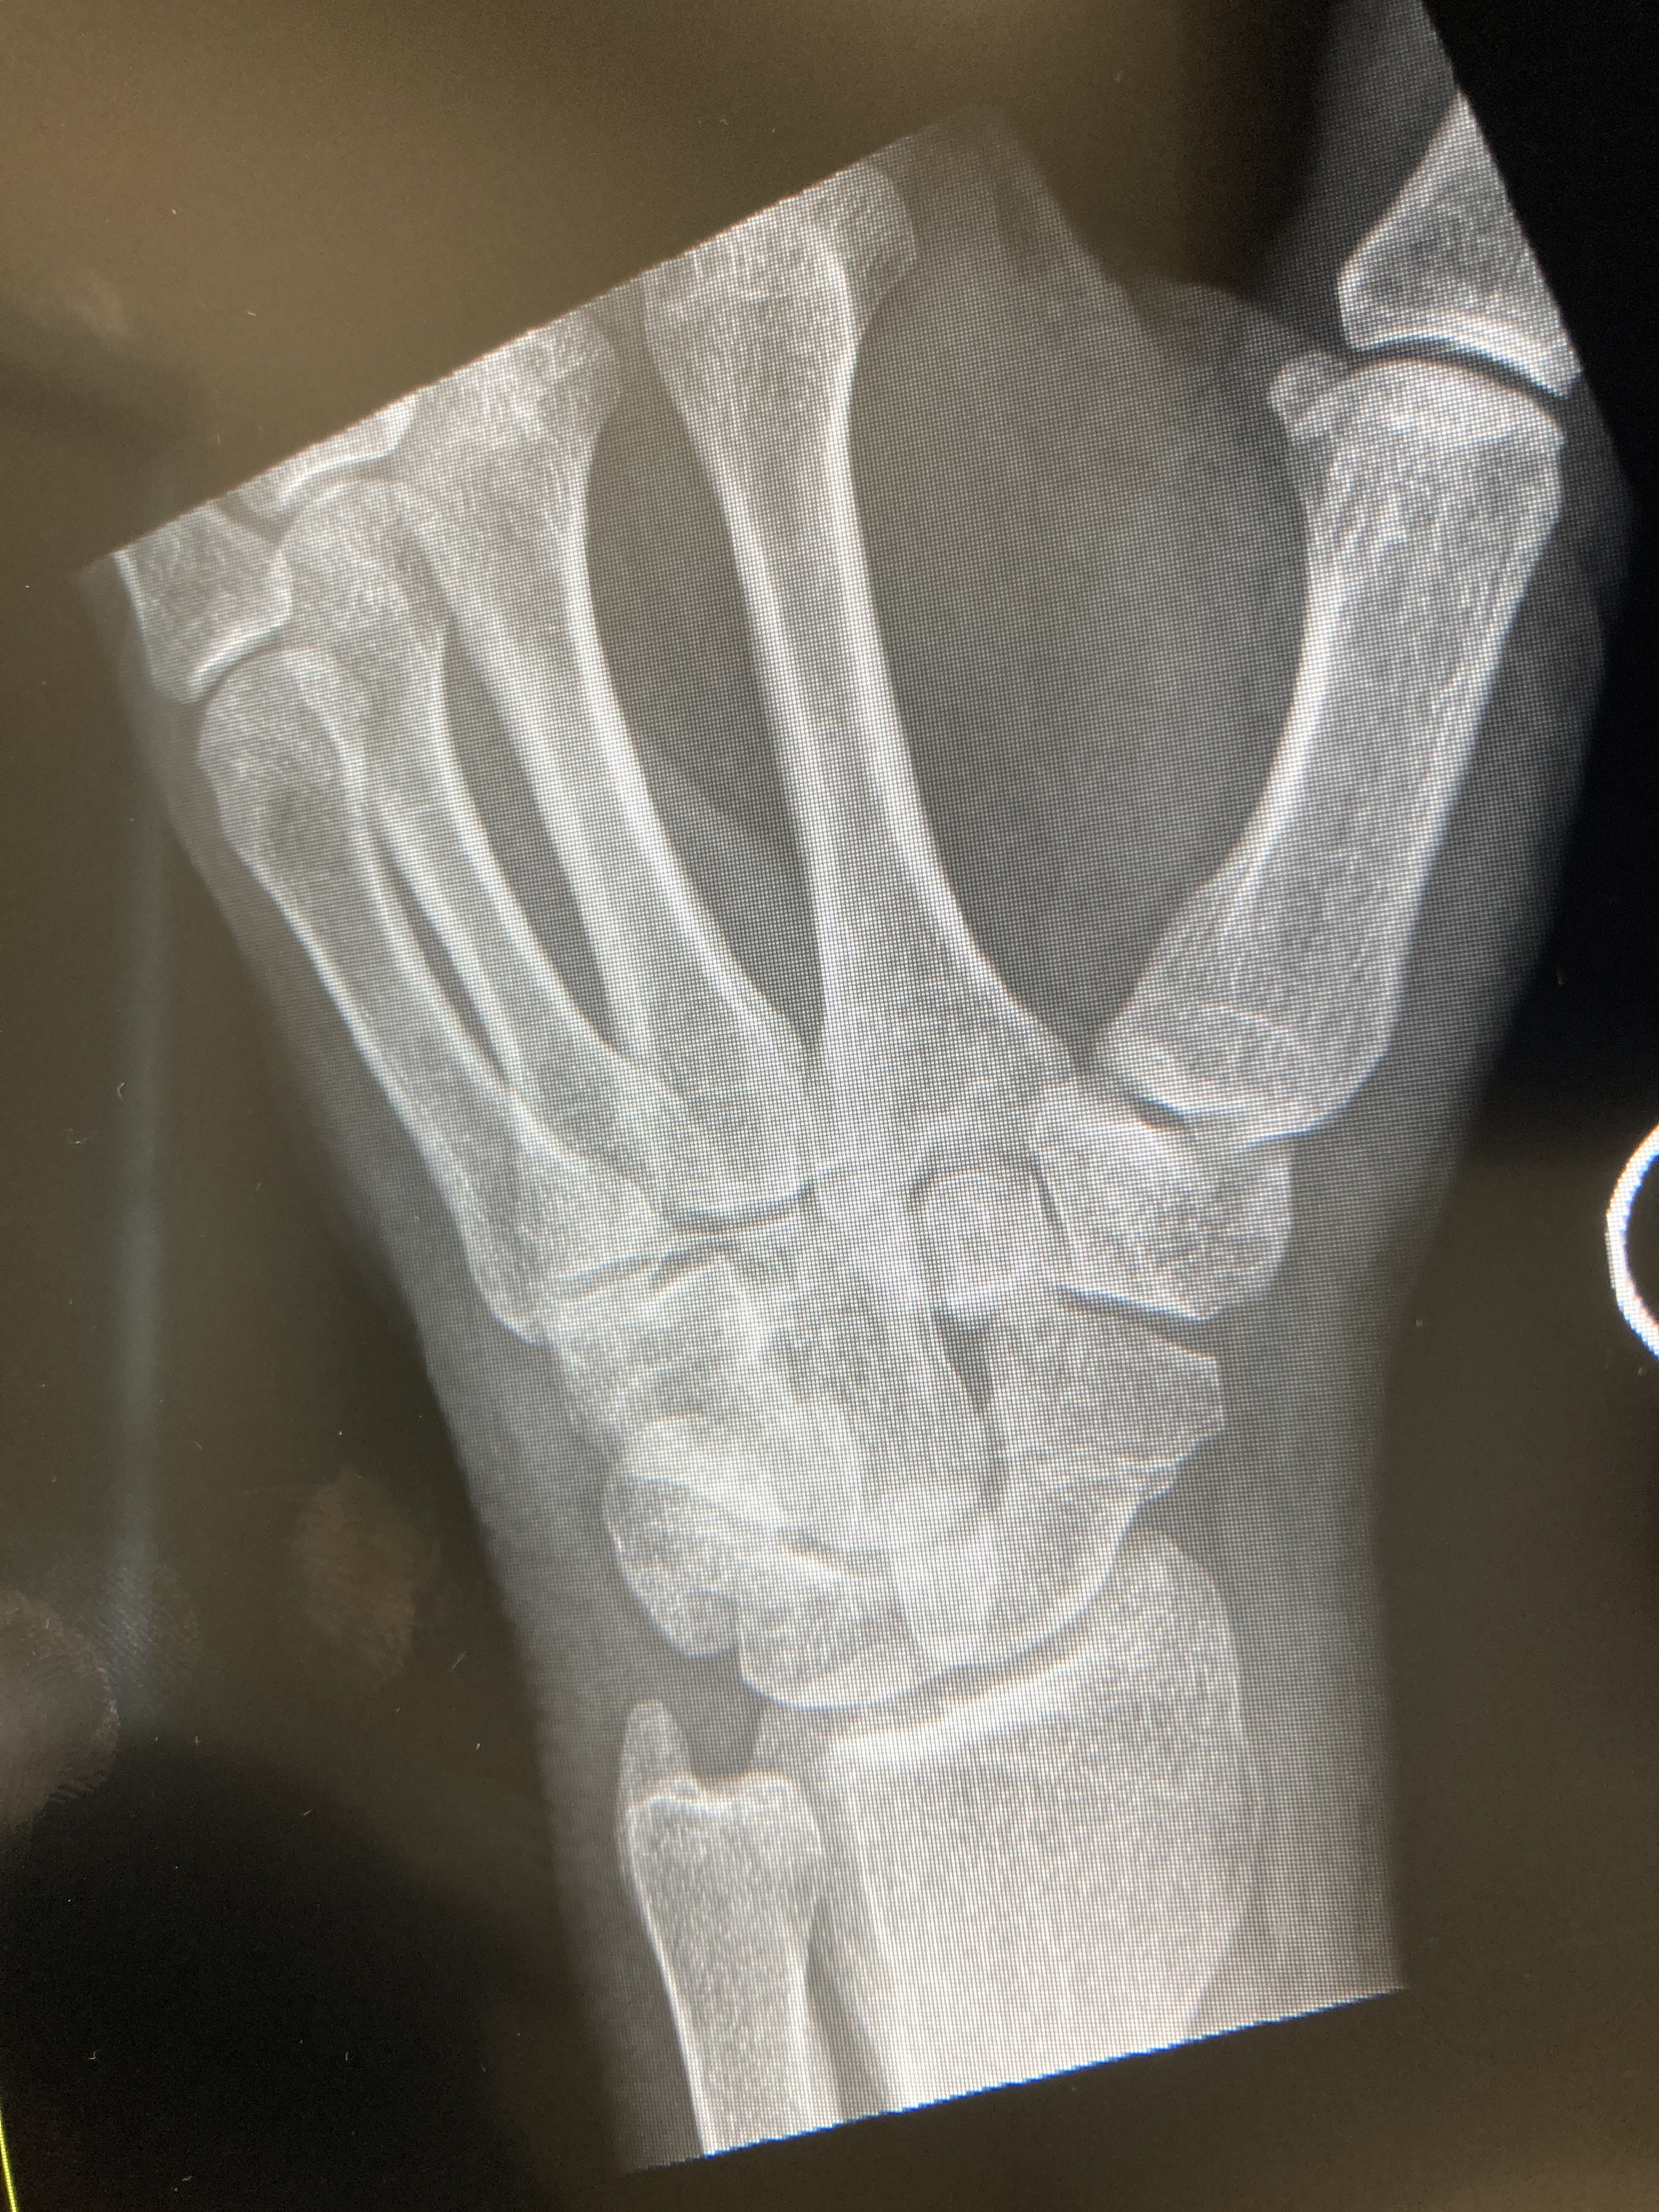

So, there is finally some light at the end of the tunnel. It’s been seven weeks since I tossed myself unceremoniously off my own roof, landing in a heap on the path below. A full day in the emergency department followed, which in itself is where I believe someone coined the phrase ‘insult to injury’. There were casts, back braces, pain and discomfort, pissing into cardboard bottles, and many x-rays and scans. Whilst I wasn’t doing any running, I certainly got my steps in traipsing up and down from the Outpatients Department in the last few weeks to get the x-rays done.

My wrist is still rather stiff and a little sore. But that was put through its paces too, and there a number of exercises to do in order to free it up. I have just tried playing the guitar, and that is still rather uncomfortable. But according to my physio (whose husband also plays guitar), playing – or attempting to, anyway – is also good exercise. In moderation.